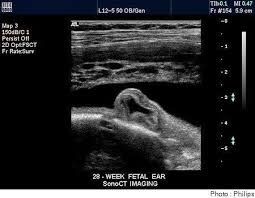

Vue de côté, le bébé regarde vers le haut, en blanc les os. Identifier les anomalies structurelles l'échographie morphologique peut détecter. L'échographie est une technique d'imagerie non irradiante utilisant les ultrasons qui sont émis par une sonde que le médecin radiologue pose sur la peau.